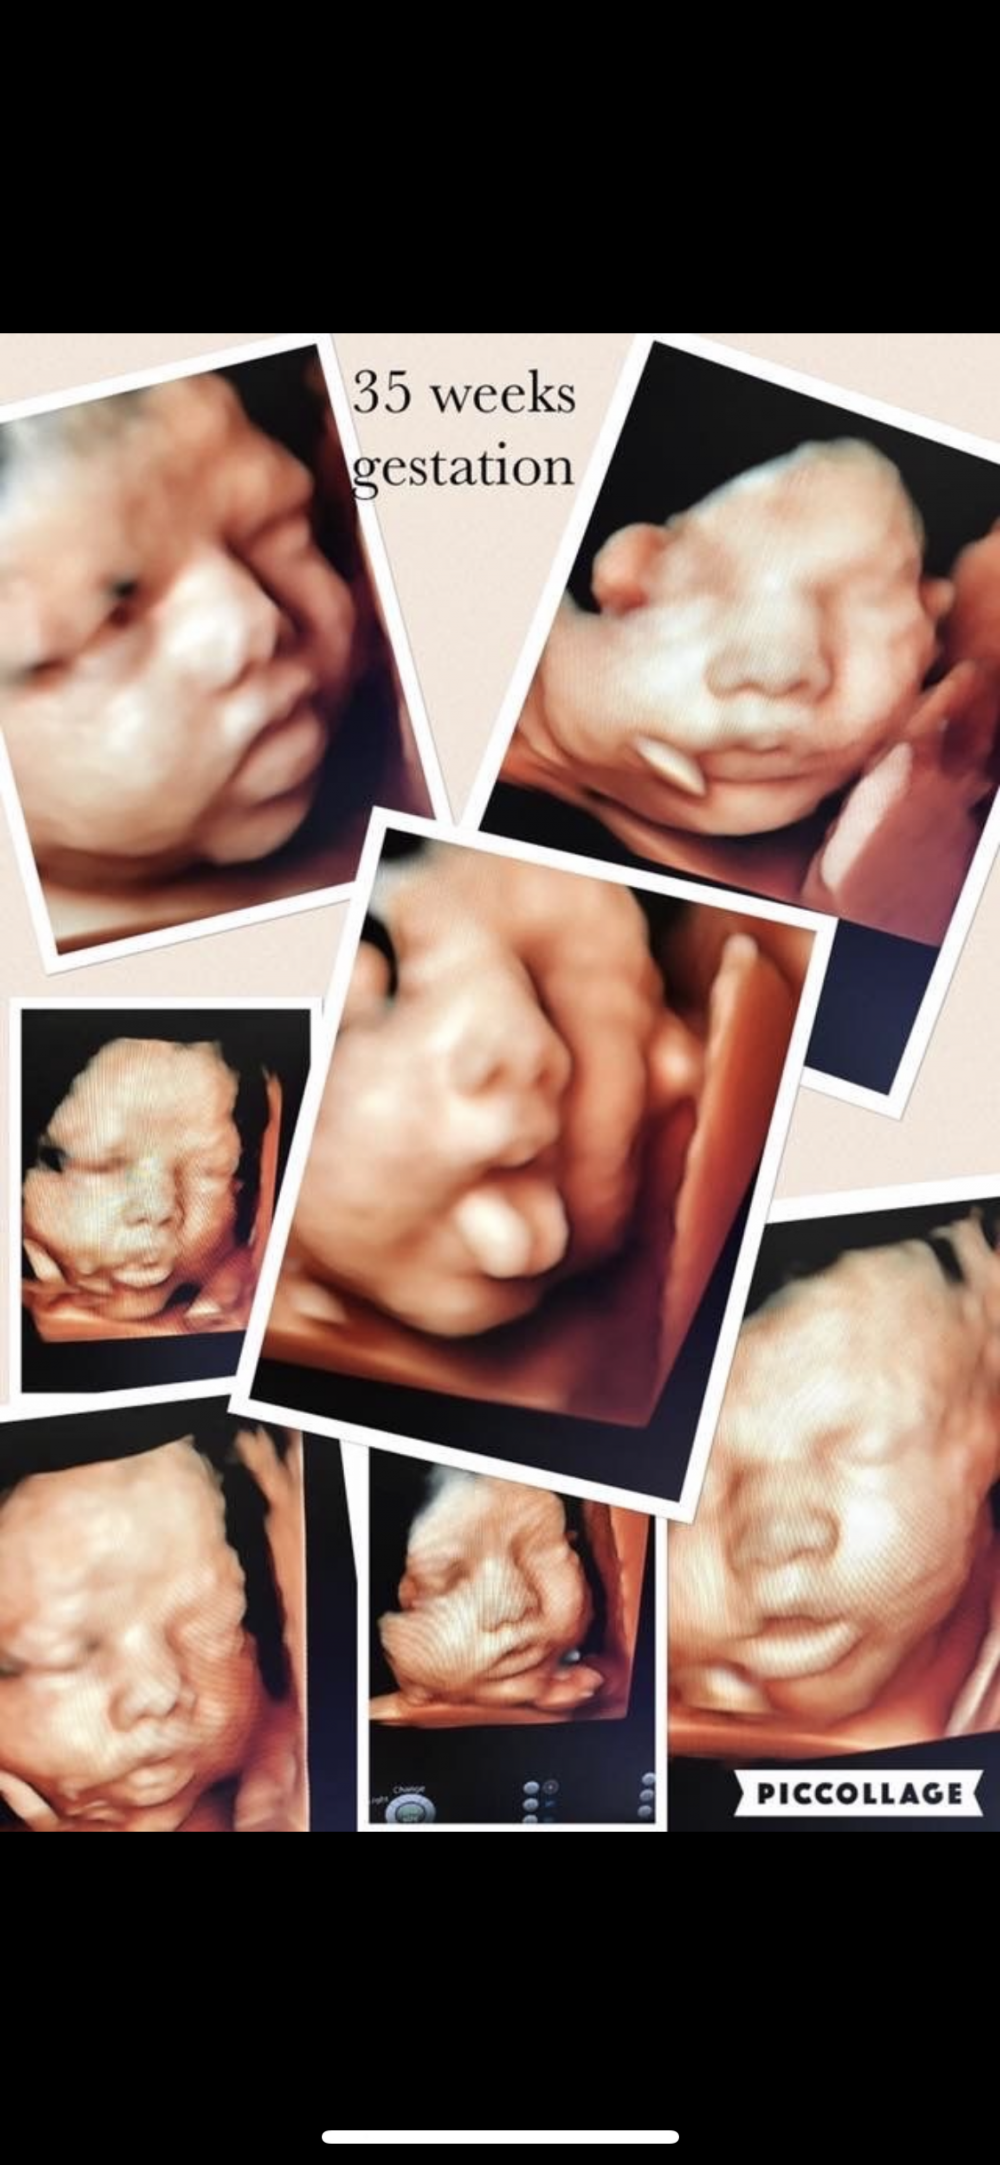

من ٢٨-٣٦ اسبوع راح يتضح لك فقط الوجه او الجسم لان الجنين حجمه صار كبير